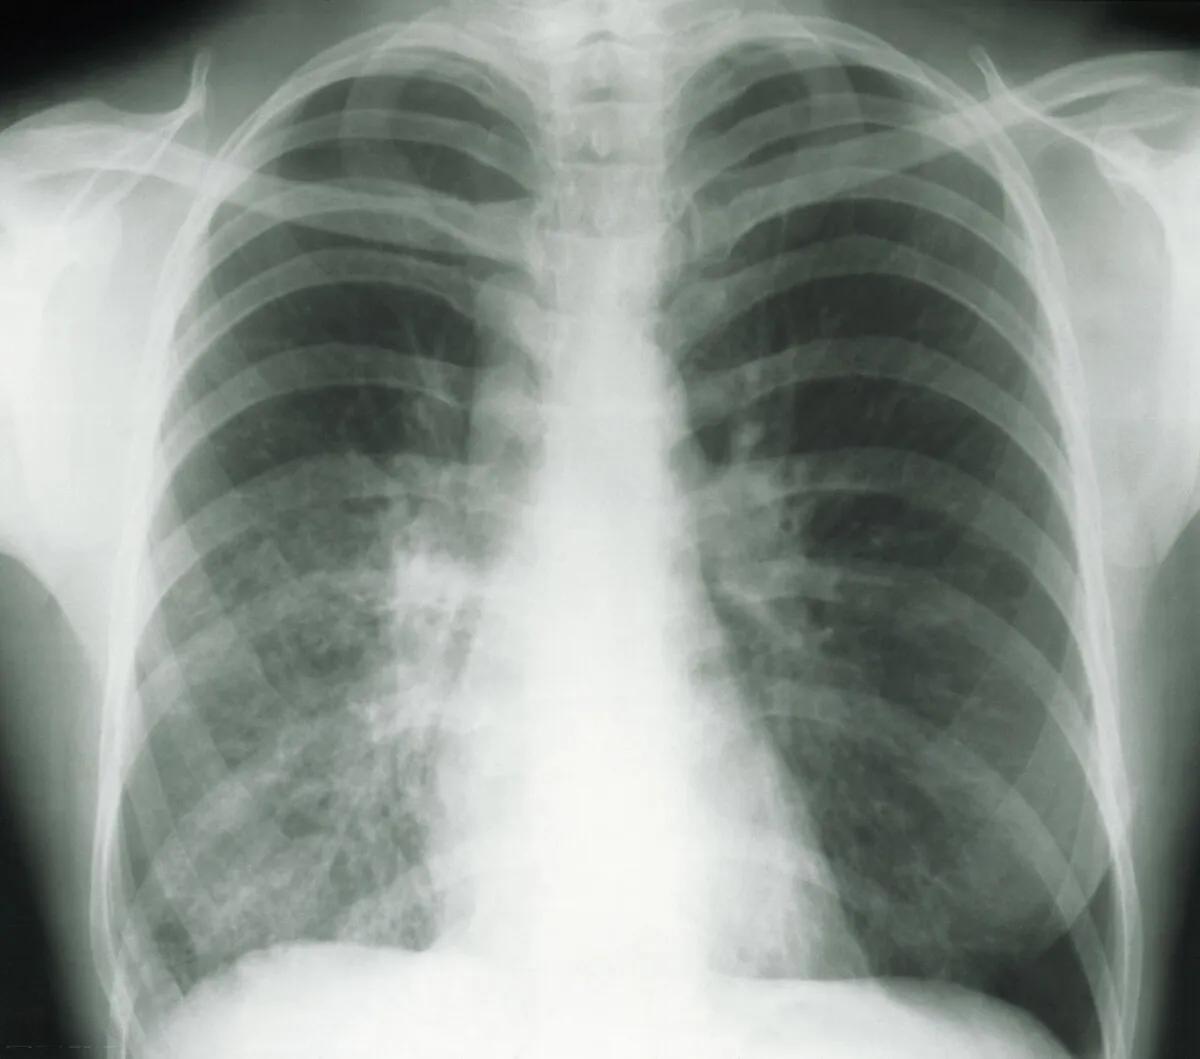

肺部CT检查中,你是否曾经看到过“磨玻璃影”或“磨玻璃结节”这样的字眼?这两个看似相似的术语,实际上有着不同的含义,而它们与肺癌的关系更是让许多人感到困惑。让我们一起来揭开这个谜题。

磨玻璃影(Ground-glass opacity, GGO)是指在CT图像上表现为密度轻微增加的云雾状阴影,其内部的血管和支气管纹理仍然可见。而磨玻璃结节(Ground glass nodule, GGN)则是指边界清楚或不清楚的肺内密度增高影,其病变密度不足以掩盖其中走行的血管和支气管影。简单来说,磨玻璃影是一种影像学表现,而磨玻璃结节则是指具有这种影像学表现的肺部结节。

那么,这两种影像表现与肺癌的关系如何呢?事实上,磨玻璃影和磨玻璃结节都可能是肺癌的早期表现之一,但并不意味着所有这些影像都与肺癌有关。根据研究,纯磨玻璃结节的恶性率约为18%,而混合性磨玻璃结节的恶性率则高达64%。这意味着,虽然大多数磨玻璃影/结节是良性的,但我们仍然需要保持警惕。